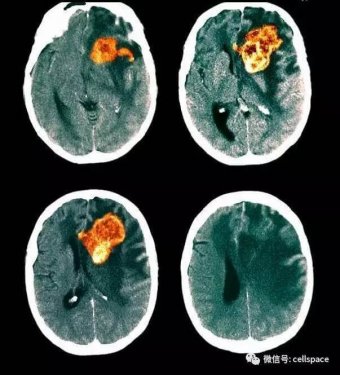

膠質(zhì)母細(xì)胞瘤(GBM)是最常見和致命的原發(fā)性惡性腦腫瘤。由于這類腫瘤惡性程度極高,所以絕大部分的患者預(yù)后極差:膠質(zhì)母細(xì)胞瘤患者經(jīng)過手術(shù)放化療等治療手段后,其生存中位數(shù)僅為15個(gè)月左右,五年生存率不到5%。

作為當(dāng)今腫瘤治療重大挑戰(zhàn)之一,膠質(zhì)母細(xì)胞瘤亟需新的療法來改善患者預(yù)后。